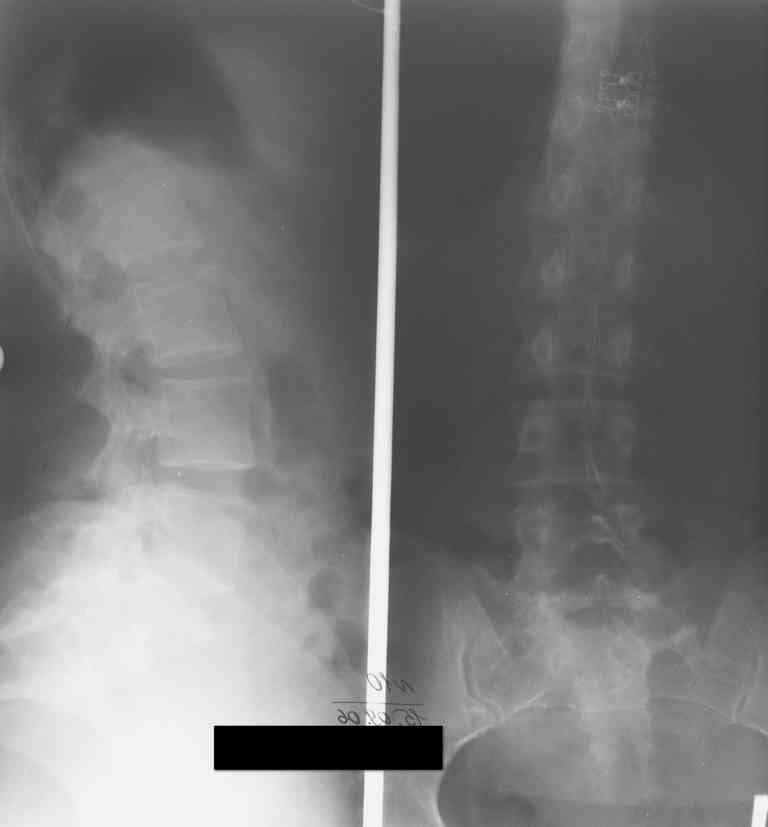

13/03/03

15/09/06

07/03/07

19/12/06

К нам в клинику поступила пациентка 30 лет с диагнозом: Постравматическая ротационная стабильная деформация тазового кольца.

Относительное укорочение левой н\конечности на 1 см. Левосторонний компенсаторный сколиоз 2 ст. Болевой синдром.

травма автодорожная в январе 2003г. Пассажирка переднего сидения ваз 2109. лечились положением по Волковичу.

С марта 2003 года жалуется на боли в тазу, ппояснице усиливающиеся при движении. В настоящее время жалобы на боли в области крестца, КПС больше слева, в пояснично-крестцовом отделе позвоночника. неприятные ощущения, щелчок при выпрямлении правого тазобедренного сустава из положения полного сгибания. боли в тазу появляются при ходьбе ч\з 100 м, так же при вставании из положения сидя, после сидения в течении 2-3 часов. при ходьбе более 100 м появпяется зябкость стоп больше справа. ходит при помощи трости в правой или в левой руке. без трости боли появляются сразу после начала ходьбы.

симптомы натяжения с обеих сторон отрицательны. С 2003г. лечится консервативно, получала ЛФК, массаж, физиолечение - без эффекта. в 2005г. лечилась в санатории с ортопедическим уклоном, получала плавание в минеральной воде, магнитотерапия, массаж, ЛФК. отмечала умеренное улучшение в течении 2 недель. Вопросы: надо ли оперировать, т.е. устранять относительное укорочение левой н\конечности и как?Если не оперировать, то как лечить консервативно? Р-граммы, КТ прилогаются.